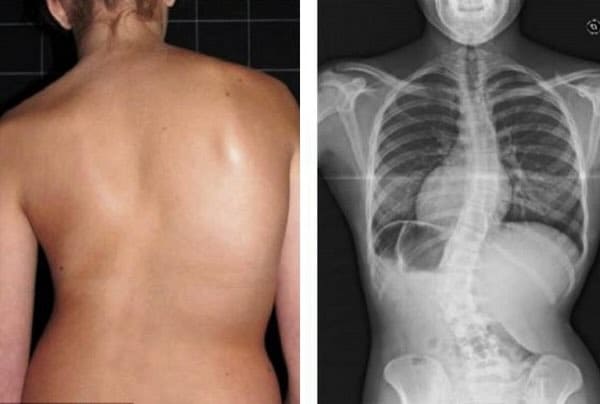

Погледнете този случай: това е гръбначният стълб на 44-годишен човек, който показва дегенеративни промени, характерни за напреднала възраст. Преди подобно разрушение се случваше след 60, а днес – още на 40. Тези промени напредват с възрастта и ако бъдат пренебрегнати, това означава риск от пълна загуба на подвижност!

Погледнете тези снимки – това е съдбата на тези, които не са реагирали навреме. Днес те са безпомощни и много от тях нямат никого, който да им помогне. Наистина ли искате такъв край?